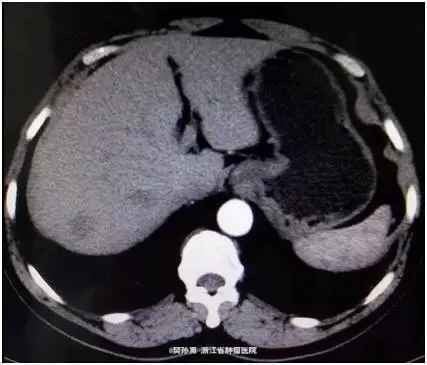

查体:心肺查体阴性,腹平软,无腹壁静脉曲张,全腹无压痛、反跳痛,腹部无包块。肝脏未触及,脾脏未触及,Murphy氏征阴性,肝、肾、脾无叩击痛,无移动性浊音。肠鸣音正常。 肿瘤标志物阴性。 CT表现:动脉期:肝包膜光整,肝脏形态正常,肝右叶可见低密度结节。大小约1.8*2.4 cm。边界模糊。门脉期:病灶强化幅度减低,边界较动脉期清晰。延迟期:病灶仍呈低密度。肝内胆管不扩张,肝门结构清晰自然,胆囊不大,壁光滑,腔内未见明显异常。脾脏、胰腺、胃、腹膜后未见明显异常。